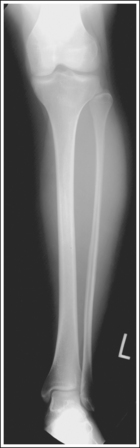

Image density is uniform across the lower leg.

• Position the thicker proximal lower leg at the cathode end of the tube and the thinner distal lower leg at the anode end to take advantage of the anode heel effect and obtain more uniform density across the lower leg.

The lower leg demonstrates an AP projection. The tibia demonstrates only minimal superimposition of the proximal and distal fibula, and the fibular midshaft is demonstrated free of tibial superimposition.

• Detecting lower leg rotation. Rotation of the lower leg can be identified on an AP lower leg projection by evaluating the relationship of the fibula to the tibia. When the patient's leg is externally (laterally) rotated, the fibula shifts toward and eventually beneath the tibia, obscuring the medial mortise (see Image 48). When the patient's leg is internally (medially) rotated, the head of the fibula draws from beneath the tibia (see Image 49).

• Positioning for fracture. For a patient with a known or suspected fracture who is unable to position both the ankle and knee into an AP projection simultaneously, position the joint closer to the fracture in the truer position. When the fracture is situated closer to the ankle, the ankle should meet the preceding requirements for a true distal lower leg AP projection (see Image 50). When the fracture is situated closer to the knee, the knee should meet the requirements for accurate positioning for a proximal lower leg AP projection. Depending on the degree of tibial and fibular rotation at the fracture site, the other joint may or may not be accurately positioned for an AP projection.